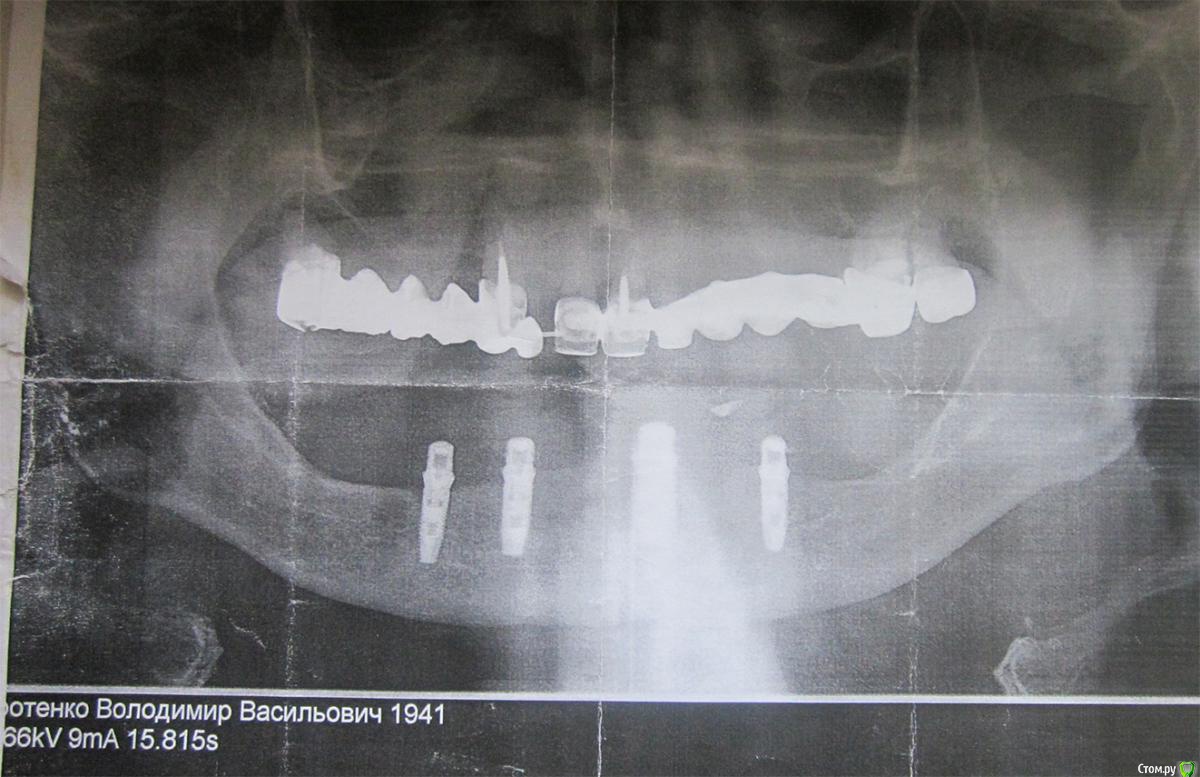

sirotenko41 Опубликовано 9 августа, 2017 Поделиться Опубликовано 9 августа, 2017 (изменено) В 1981 знаменитый автор первых имплантов доктор Эвальд Варес, вопреки всем правилам поставил стационарный протез верхней челюсти( на основе акрила) на 7-1-1-3-8 зубах. К сожалению в 90-е его выжили со Львова и он перебрался в Донецкий мед.институт. За это время у меня полетели все зубы на нижней челюсти и в 2011 друг и ученик Вареса Мирон Миронович Угрин поставил мне стационарный протез нижней челюсти на 4-х имплантах. Так как за 30 лет протез верхней челюсти прогнулся в районе 1-7, то посоветовал заменить его. Менял я протез у своего лечащего врача. Он отказался ставить такой длинный мостик из акрила. Согласился только на металлокерамику, которой Варес не признавал. В конце 2014 коронка на 7 зубе расцементировалась, а корни сгнили. Он предложил мне заменить стационарный протез съёмным. Однако, когда антагонистом является стационарный протез на имплантах, то ему нужна равномерная нагрузка. 8-ка у меня парадантозная и её тоже нужно рвать. Значит, частично съёмный протез будет держаться на мостике 1-1-3 и давить ночью на передний правый имплант. Я пошёл на консультацию к Угрину и он сказал, что допустим только полный съёмный протез верхней челюсти или стационарный на имплантах, который сейчас стоит 524000руб, что мне пенсионеру, не доступно ( импланитрование нижней челюсти он мне и ещё сотне ветеранов делал бесплатно по акции, за что и был наказан фискалами). Так что приходится ставить полный съёмный протез верхней челюсти, а для этого вырвать оставшиеся 5 зубов. Так как полный съёмный протез закрывает нёбо, меняет дикцию и резко ухдшает вкусовое восприятие, то я постарался ставить дентин под коронки и протянуть время жизни стационарного протеза. Увы, сейчас расцементировались уже все коронки и тянуть с заменой проьтеза дальше нельзя. Меня интересует, как лучше удалить эти оставшиеся 5 зубов, вернее корней - передние коронки у меня на корнях со вкладками, восьмёрка удалится легко, так что проблематичны только 7-ка у которой крупный корень в районе восьмёрки, а вот 2 другие корня куда-то мигрировали. Кроме того проблема с клыком Изменено 9 августа, 2017 пользователем sirotenko41 Ссылка на комментарий